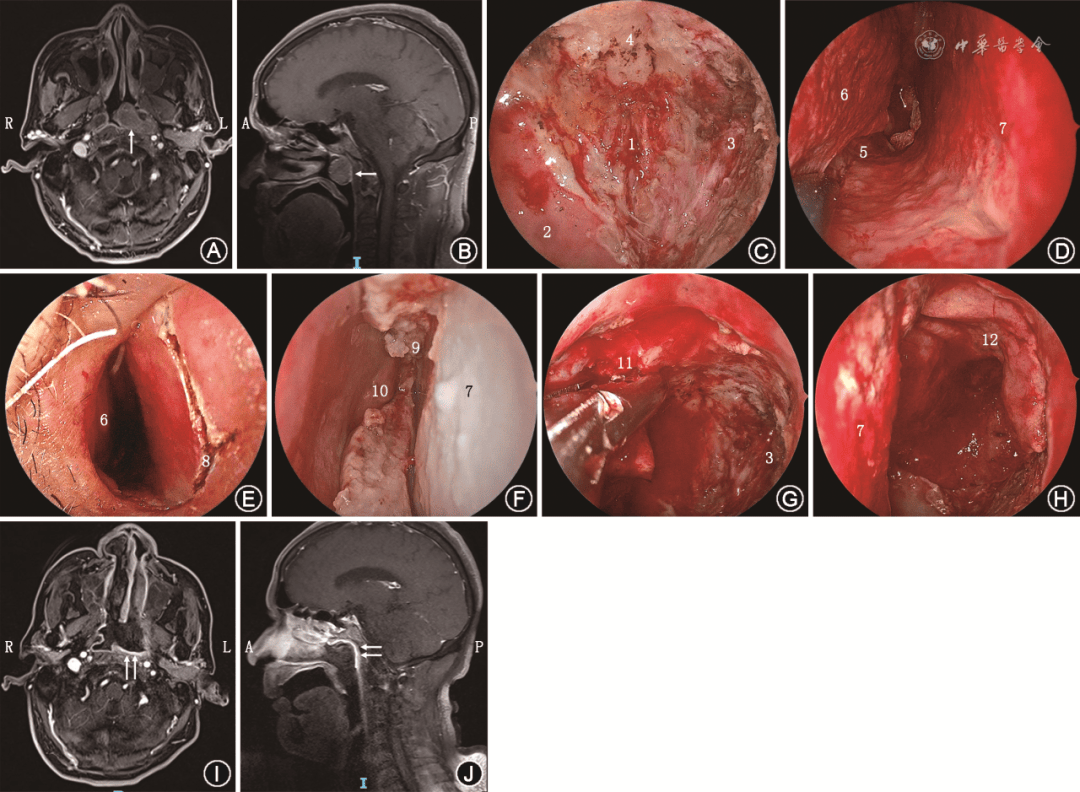

短篇论著 | 带蒂鼻中隔黏膜瓣静脉系统的解剖学研究及其在鼻颅底修复